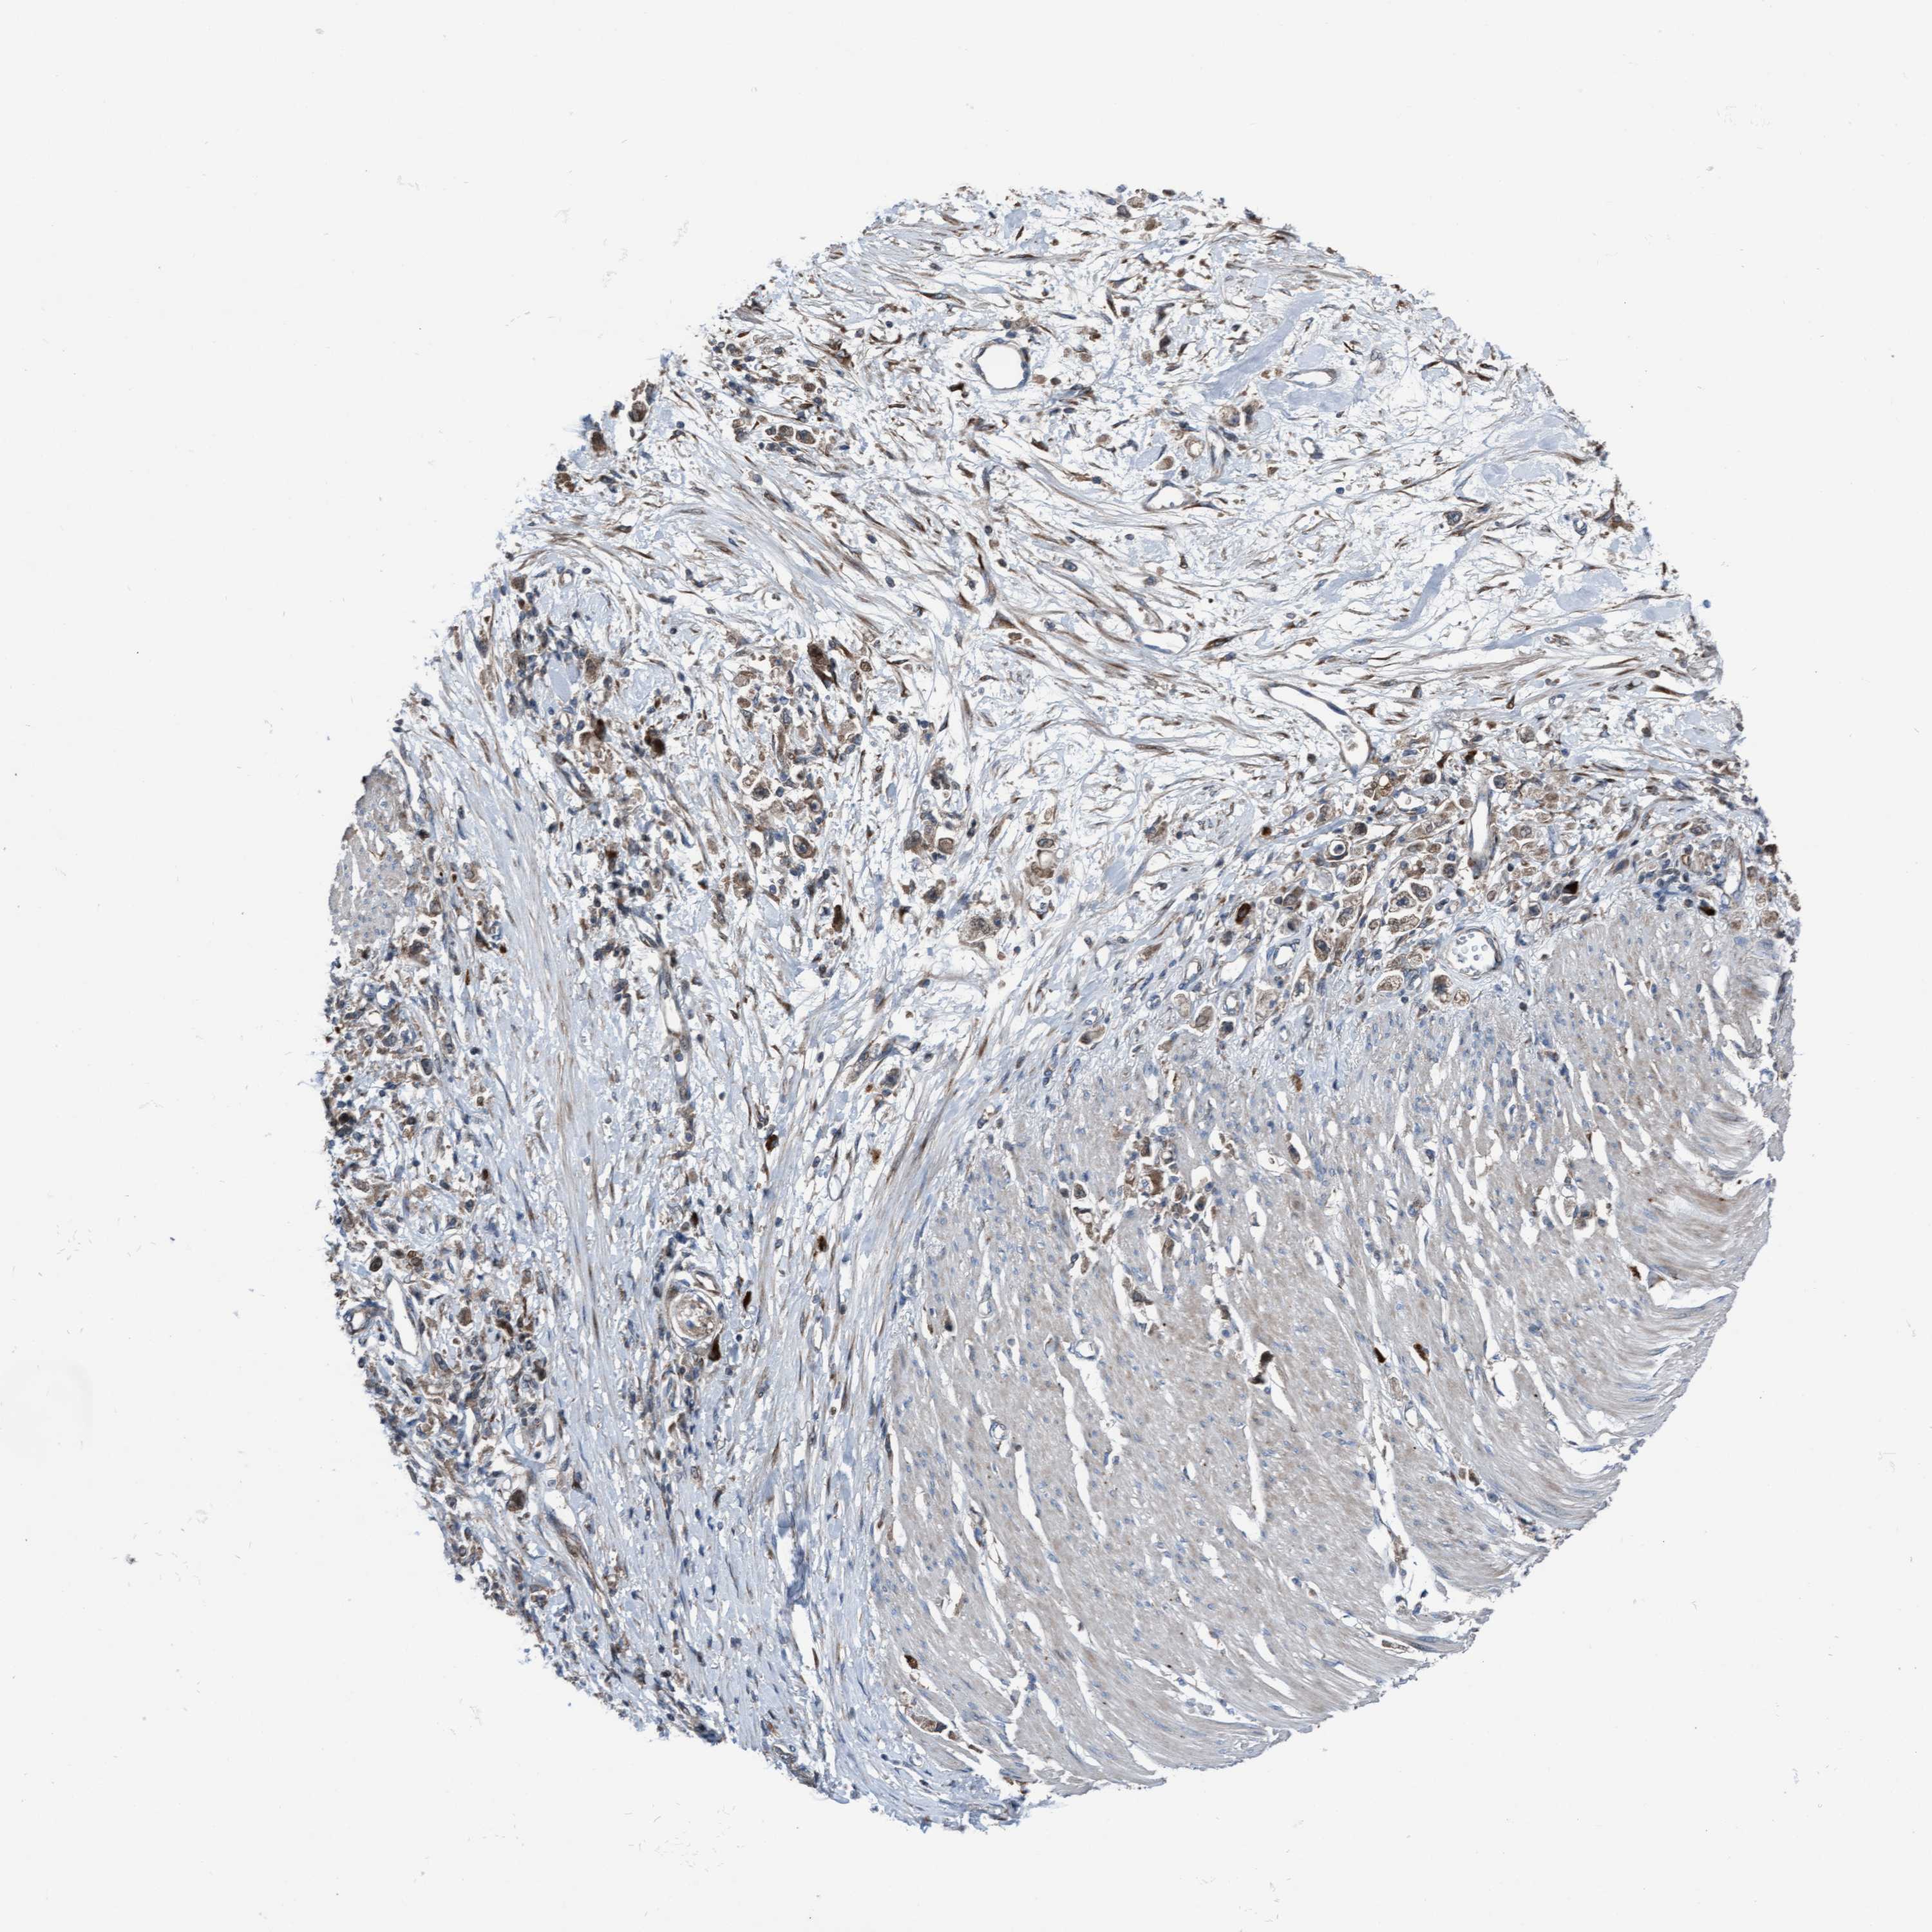

STOMACH CANCER - Protein expressioni

A mouse-over function shows sample information and annotation data. Click on an image to view it in a full screen mode. Samples can be filtered based on level of antibody staining by selecting one or several of the following categories: high, medium, low and not detected. The assay and annotation is described here.

Note that samples used for immunohistochemistry by the Human Protein Atlas do not correspond to samples in the TCGA dataset.

Antibody stainingi

Antibody staining in the annotated cell types in the current human tissue is reported as not detected, low, medium, or high, based on conventional immunohistochemistry profiling in selected tissues. This score is based on the combination of the staining intensity and fraction of stained cells.

Each image is clickable and will lead to virtual microscopy that enables deeper exploration of all samples and also displays staining intensity scores, fraction scores and subcellular localization as well as patient and tissue information for each sample.

Antibody HPA023074

Staining

High

Medium

Low

Not detected

Intensity

Strong

Moderate

Weak

Negative

Quantity

>75%

75%-25%

<25%

None

Location

Nuclear

Cytoplasmic/membranous

Cytoplasmic/membranous,nuclear

Adenocarcinoma, NOS